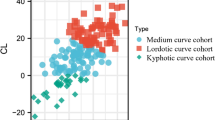

In neutral posture, the average neural foraminal area ranged from 33.0 to 55.5 mm2 and the mean neural foraminal area of all cervical segments was 43.2 mm2 (±15.6 mm2). The mean neural foraminal area for each level was C2–C3: 54.2 mm2 (±13.5 mm2) C3–C4: 41.9 mm2 (±17.7 mm2), C4–C5: 39.1 mm2 (±11.6 mm2), C5–C6: 33.0 mm2 (±12.9 mm2), C6–C7: 33.7 mm2 (±12.2 mm2) and C7-T1: 55.5 mm2 (±9.7 mm2) (Fig. 7; Table 3).

Mean neural foraminal areas of cervical segments in the neutral posture of all specimens (n = 13). Neutral posture is depicted as posture III in Fig. 3